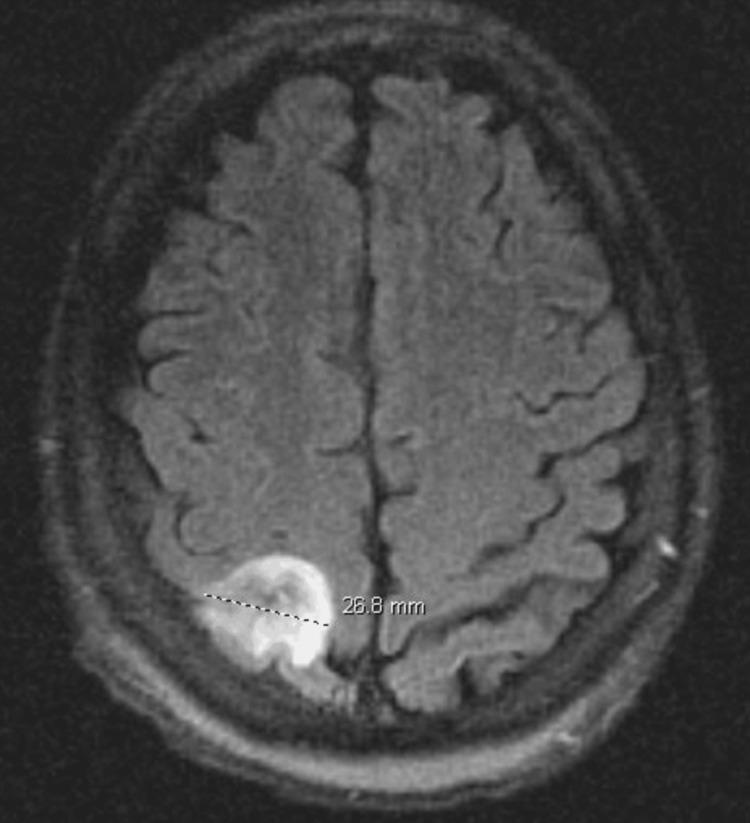

Glucocorticoids are ubiquitously used by physicians for a myriad of diseases. Though powerful and potentially lifesaving, sometimes the dangerous side effects are not at the forefront of our medical decision-making. By immunosuppressing patients, glucocorticoids can place patients at increased risk for not only the metabolic effects of chronic glucocorticoid use but also increased risk for opportunistic infections. Patients at increased risk include those on prolonged courses or those that require high doses. We report a case of a 34-year-old man who was initiated on glucocorticoids for an unknown rheumatologic disease and presented with generalized weakness, fatigue, nausea, and vomiting. The patient experienced a seizure, which prompted head imaging. A mass was found and eventually biopsied, which was notable for The patient was initiated on antifungals for CNS aspergillosis and recovered.